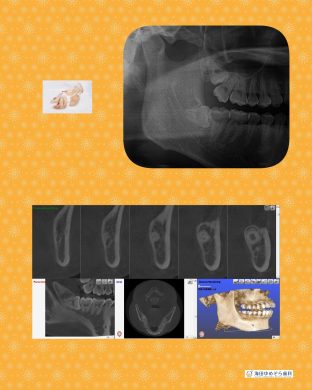

横向き親知らずの抜歯症例

最近の症例

院長はこのような横向きに埋まっている抜歯ケースも

1000症例以上の手術実績あり☆

横に埋まっている場合はCT撮影で安心です☆